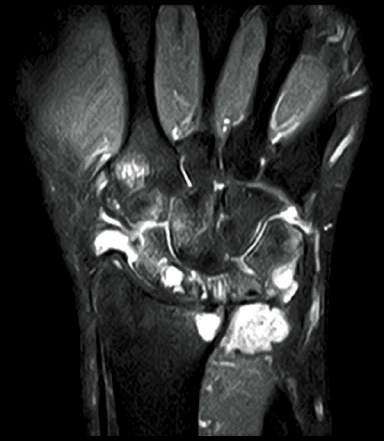

FatSep-T2*WI

FatSep-T2WI